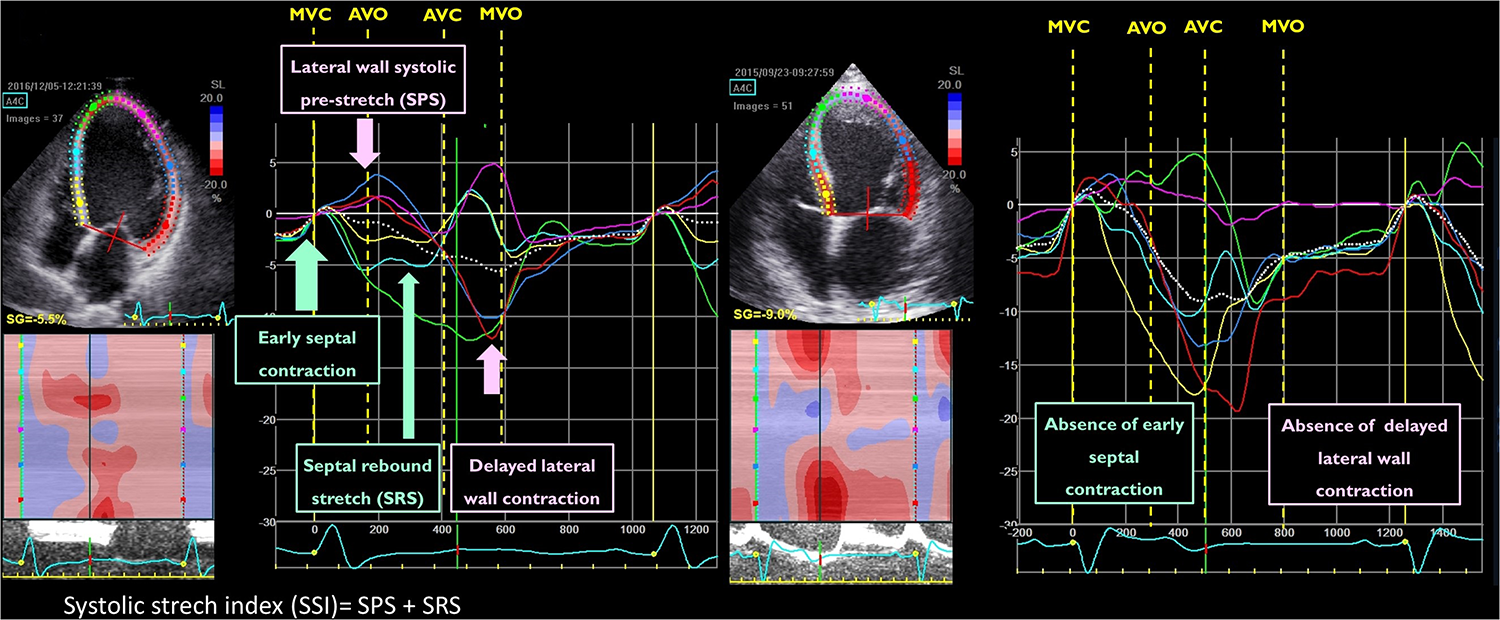

Starting from the visual analysis of strain curves obtained in a 4-chamber view in the septal and lateral wall, Risum et al. have shown that the “typical left bundle branch block” (LBBB) strain pattern is characterized by an early shortening of the septal wall, before the opening of the aortic valve, with concomitant stretch in the lateral wall. This early septal activation is followed by immediate lengthening (rebound stretch) and causes a delayed lateral wall peak contraction (Figure 3). This specific activation pattern has been shown to improve the prediction of LV reverse remodelling and prognosis after CRT (24). Computer simulation studies have demonstrated that the progressive decline in LV contractility is associated with a loss of the septal-to-lateral wall interplay typical of LBBB, such explaining the poor CRT-response in these patients (45). The sum of the posterolateral systolic prestretch and septal systolic rebound stretch, referred to as systolic stretch index (SSI) can be used to quantify the electromechanical substrate of dyssynchronous heart and has been shown to be associated with both CRT-response and prognosis (9, 25). Interestingly, an SSI > 2.6% was able to predict death or HF hospitalisation (HR: 2.08; 95% CI: 1.27 to 3.41, p = 0.004) and overall survival (HR 5.08; 95% CI: 1.94 to 13.31, p < 0.001) also in patients with a QRS width 120 to 149 ms or non-LBBB morphology (Figure 3).

Figure 3

Example of the qualitative analysis of strain curves in a patient with a “typical” left bundle branch block (left panel) and “atypical” left bundle branch block (right panel). The systolic stretch index (SSI) quantification is exemplified in the same picture (left panel).